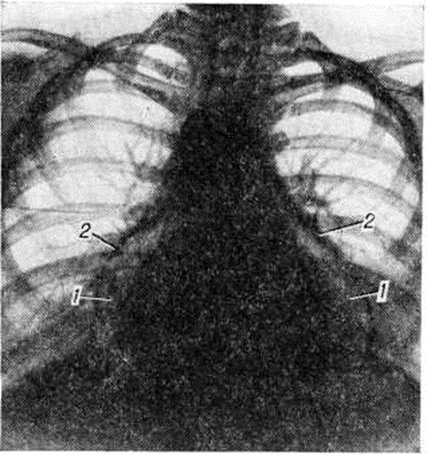

При больших количествах выпота в полости перикарда диагностическое значение приобретают признаки сдавления органов средостения (затруднённое глотание, охриплость голоса) и тампонады сердца (приступы слабости с холодным липким потом, снижение АД, частый малый пульс и другие). Кроме резкого расширения границ сердца, отмечается снижение громкости его тонов, отмечаются видимые гемодинамические нарушения — цианоз лица и шеи, значительная набухлость шейных вен. Специфическое диагностическое значение имеет выявление двойного инспираторного феномена — парадоксального пульса и набухания шейных вен в фазу вдоха. Окончательное подтверждение диагноза экссудативного Перикардит получают при рентгенологическое исследовании (смотри полный свод знаний ниже) или с помощью эхокардиографии (смотри полный свод знаний), а характер экссудата (хилёзный, холестериновый, серозный, гнойный и другие) уточняется после пункции перикарда. Эхокардиография позволяет надёжно обнаружить выпот в перикардиальной полости даже при малых его количествах (50—100 миллилитров) по возникновению эхонегативного пространства между задней стенкой левого желудочка и оттеснённым кзади париетальным листком перикарда. При больших выпотах этим методом выявляется слой жидкости также над передней стенкой правого желудочка—возникает феномен «плавающего сердца». Адгезивный (слипчивый) Перикардит при наличии данных о Перикардит в анамнезе может быть заподозрен в случае стабилизации у больного одышки, при появлении жалоб на сухой кашель, боли в груди, слабость. До проведения рентгенологическое исследования диагноз устанавливается при наличии систолического втяжения верхушечного толчка, протодиастолического тона броска и выявлении диастолического венозного коллапса. О констриктивном Перикардит свидетельствуют выраженная одышка без ортопноэ, значительная слабость и утомляемость больных при физической нагрузке, признаки высокой венозной гипертензии с цианозом и отёчностью лица и шеи («воротник Стокса», «консульская голова»), наличие увеличенной печени и асцита при отсутствии, как правило, отёков на ногах. Верхушечный толчок сердца обычно не определяется; при аускультации сердца часто обнаруживается протодиастолический тон броска, иногда добавочный пресистолический тон. Изменяются кривые давления в правых камерах сердца (рисунок 2). В период расслабления давление в правом желудочке резко снижается, что отражается на кривых давления протодиастолическим «провалом»; в фазу быстрого наполнения оно повышается, достигая уровня центрального венозного. При этом на кривых давления формируется так называемый теледиастолическое плато. На кривой пульса яремной вены (рисунок 3) нередко регистрируется характерная двухволновая кривая, представленная положительными волнами а и v, вершины которых уплощены, как бы срезаны, и крутыми спадами. Волна с, отражающая сокращение правого желудочка, уменьшается. Различия в степени уменьшения объёма правого желудочка и переполнения вен обусловливают весьма вариабельные формы кривой венного пульса, что ограничивает её диагностическое значение. Электрокардиографическое исследование занимает одно из важнейших мест в диагностике острого сухого Перикардит Наиболее ранним признаком острого Перикардит на ЭКГ (рисунок 4) является конкордантный подъём сегмента ST обычно во всех стандартных отведениях (наибольший во II отведении), а также в грудных. Однако при локализации воспалительного процесса на ограниченном участке смещение сегмента ST может отмечаться в двух или даже только в одно из стандартных отведений. Через 1—2 дня сегмент ST опускается ни же изолинии, затем постепенно в течение 3—20 дней — возвращается к изолинии, несмотря на продолжающийся воспалительный процесс в перикарде. При медленно прогрессирующих Перикардит смещения сегмента S1 обычно обнаружить не удаётся. Положительный и даже несколько увеличенный на ранних стадиях Перикардит зубец Т затем постепенно уплощается и через 10—15 дней становится отрицательным или двухфазным в тех отведениях, в которых происходила динамика сегмента ST. Отрицательные зубцы Т сохраняются значительно длительнее, чем смещение сегмента ST. При хронический Перикардит инверсия зубца Т нередко остаётся постоянной. В случае вовлечения в процесс перикарда предсердий воз можно изменение формы конечной отрезка зубца Р и смещение от изоэлектрической линии сегмента PQ. Начальные изменения ЭКГ при экссудативном Перикардит не отличаются от описанных при сухом Перикардит, в дальнейшем отмечается снижение вольтажа зубцов ЭКГ, электрическая альтернация желудочковых комплексов. Для изменений ЭКГ при констриктивном Перикардит наиболее характерна триада: расширенный высокий зубец Р, низковольтный комплекс QRS, отрицательный зубец Т (во всех стандартных и прекардиальных отведениях). Кроме снижения вольтажа, наблюдаются изменения формы комплекса QRS: расщепление, расширение, образование зазубрин, углубление зубца Q, которые свидетельствуют о глубине вовлечения в патологический процесс миокарда. Увеличенный зубец Р резко контрастирует с низковольтным комплексом QRS, свидетельствуя о рабочей гипертрофии предсердий. После перикардэктомии постепенно увеличивается вольтаж желудочковых зубцов ЭКГ, нередко нормализуется зубец Т. Рентгенологическое исследование мало информативно при фибринозном (сухом) Перикардит, но имеет большое, иногда решающее значение для диагностики экссудативных и адгезивных форм перикардита. Экссудативный Перикардит в начале своего развития проявляется изменением конфигурации сердечной тени за счёт выпрямления талии сердца; в дальнейшем она может стать даже выпуклой. По мере накопления выпота сердечная тень становится все более сферической, силуэт сердца теряет свою дифференцировку на дуги, отмечается быстрое увеличение тени сердца с превалированием её поперечного размера над длинником, смещение вправо дуги правого предсердия. Исчезает тень нисходящей части аорты, сосудистый пучок расширяется за счёт верхней полой вены и представляется относительно укороченным. Кардиодиафрагмальные углы, особенно правый, заостряются. При повторных исследованиях отмечается быстрая динамика увеличения размеров тени сердца. При изменении положения тела форма сердечной тени меняется. Амплитуда пульсации контуров сердца уменьшается вплоть до полного её исчезновения при сохранении пульсации крупных сосудов. Лёгочный рисунок остаётся нормальным, несмотря на выраженное увеличение размеров сердечной тени (рисунок 5). Решающим диагностическим методом, сочетающим и терапевтическое воздействие, является пункция перикарда с наложением искусственного пневмоперикарда (смотри полный свод знаний) и особенно исследование с двойным контрастированием перикарда. Перикард утолщён, особенно у диафрагмы, что хорошо видно при наложении пневмоперикарда (рисунок 6); иногда в нем встречаются массивные обызвествления.